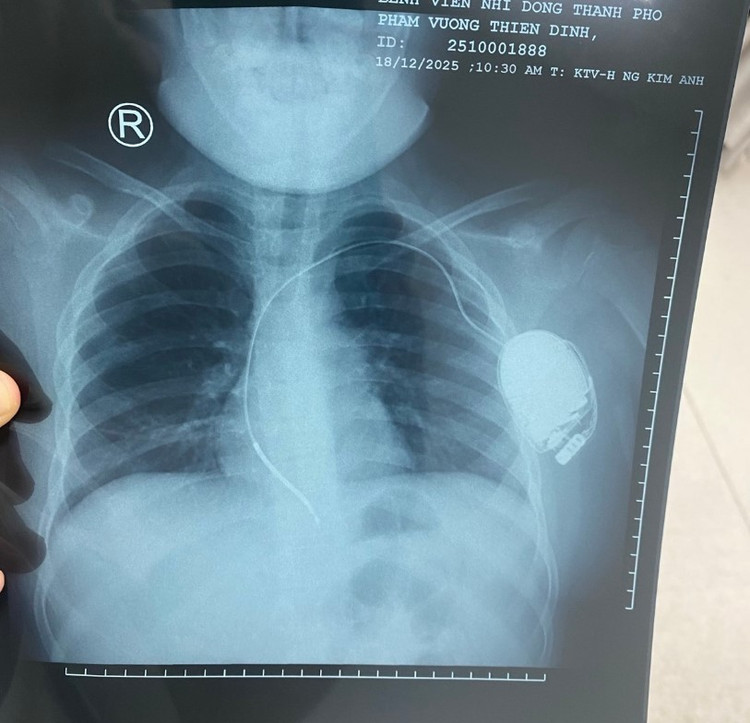

ngung-tim-2.jpg

ngung-tim-3.jpg

Máy khử rung tim tự động trong lồng ngực trẻ sau can thiệp trên phim chụp - Ảnh BVCC